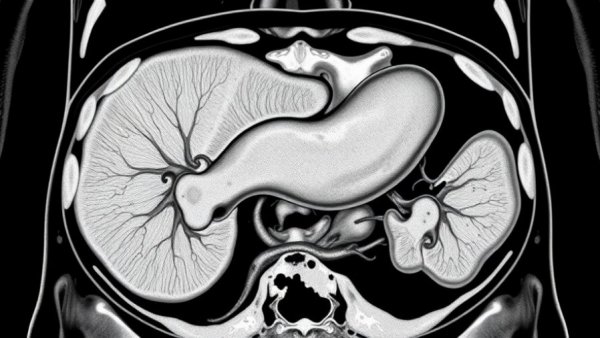

Abdominal scan highlighting pancreas for early detection of pancreatic cancer.